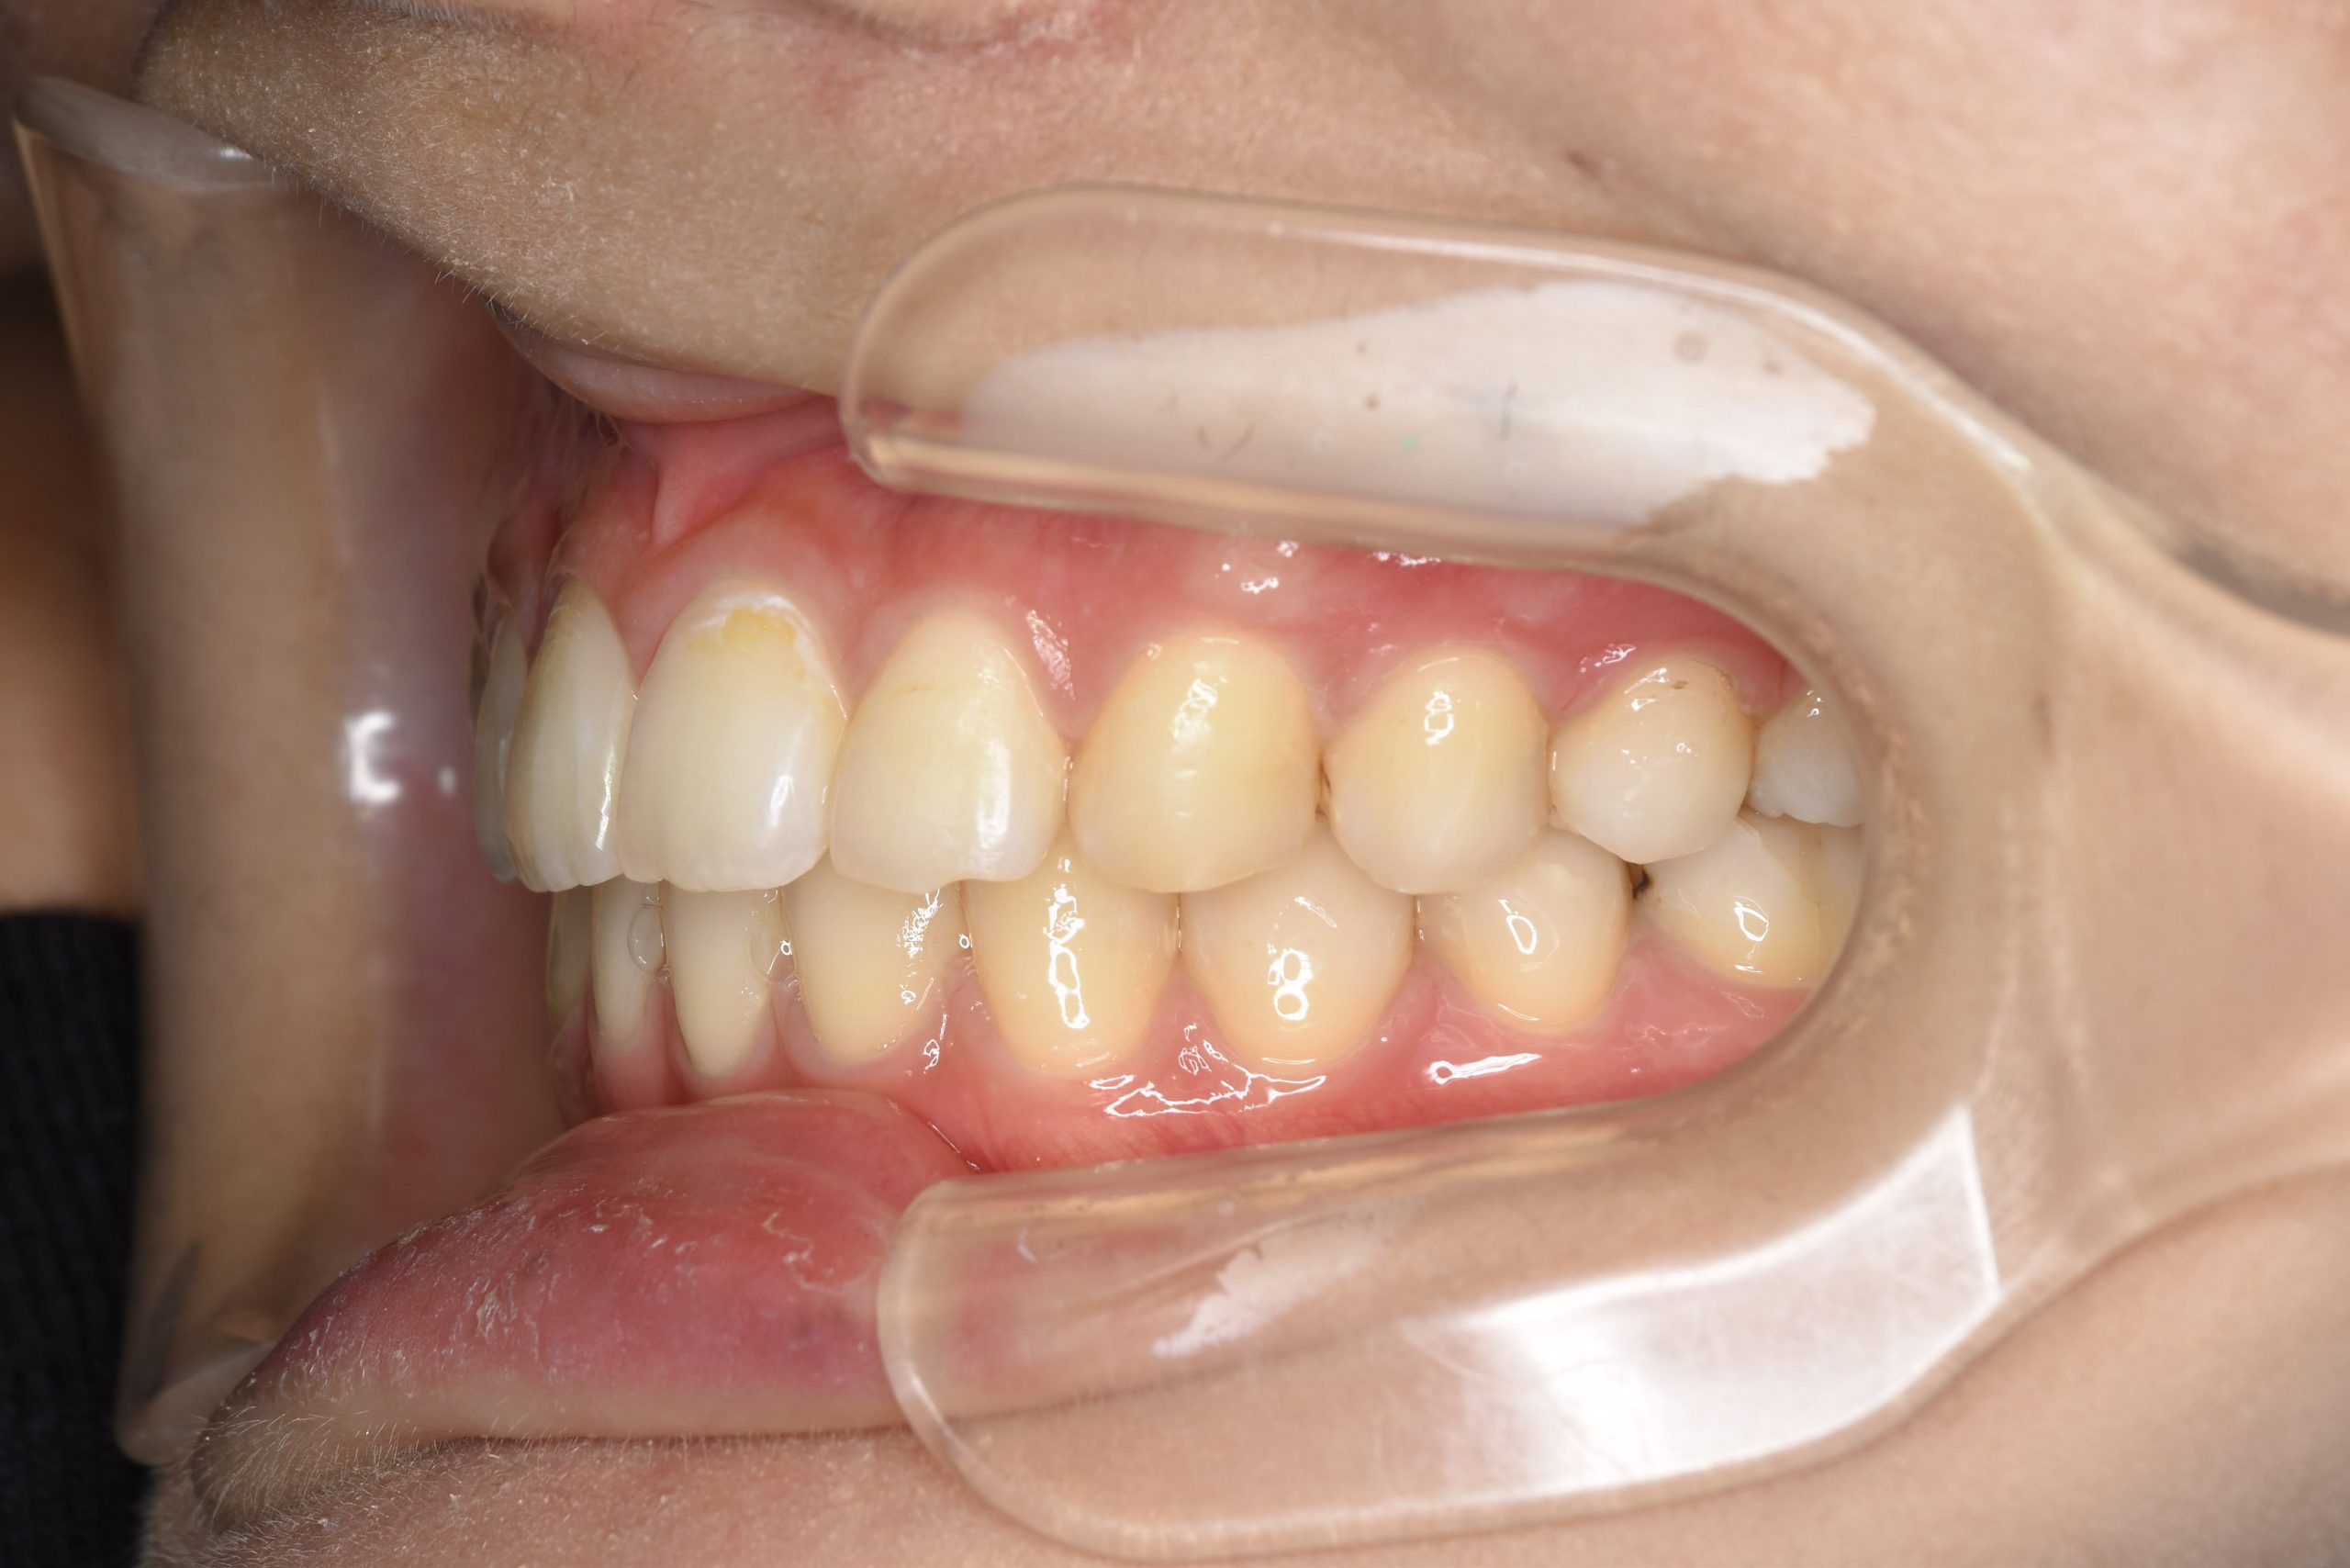

アフター

ワイヤー矯正治療|症例_009

施術内容 MSEと下顎リンガルアーチを用いて上下顎骨を拡大した。

その後マルチブラケット装置とミニインプラントを用いて非抜歯で歯牙を配列した。

下顎前歯が1本先天性欠損であったが、良好な咬合を獲得した。口元の突出感と鼻閉症状は改善された。